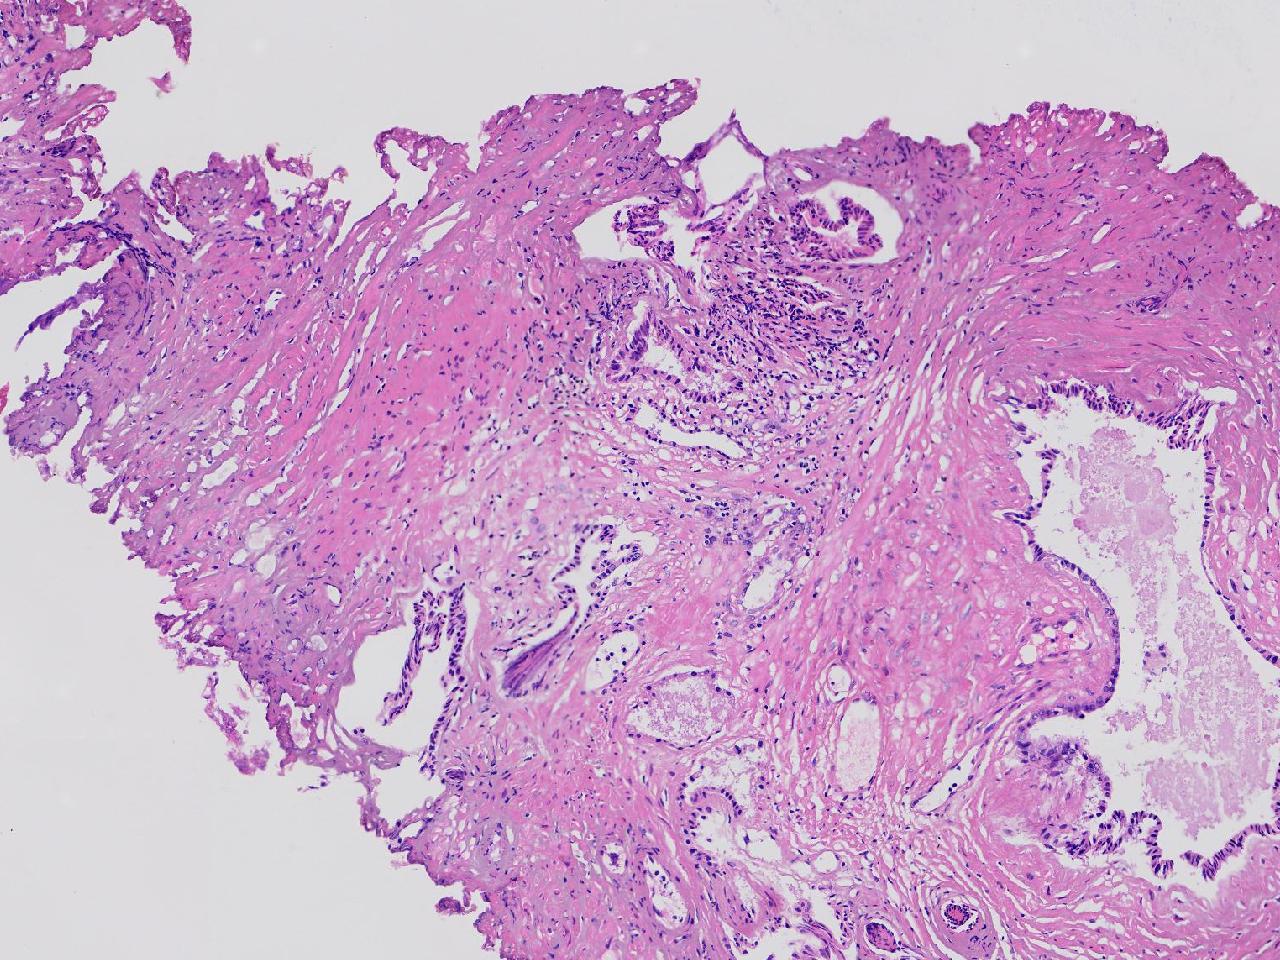

这些腺体有问题吗?

性别

男

年龄

77岁

男,77岁,排尿困难2年,尿潴留3天。

标本名称

电切前列腺组织

大体所见

条索状软组织多块,5X5X4厘米。

图1